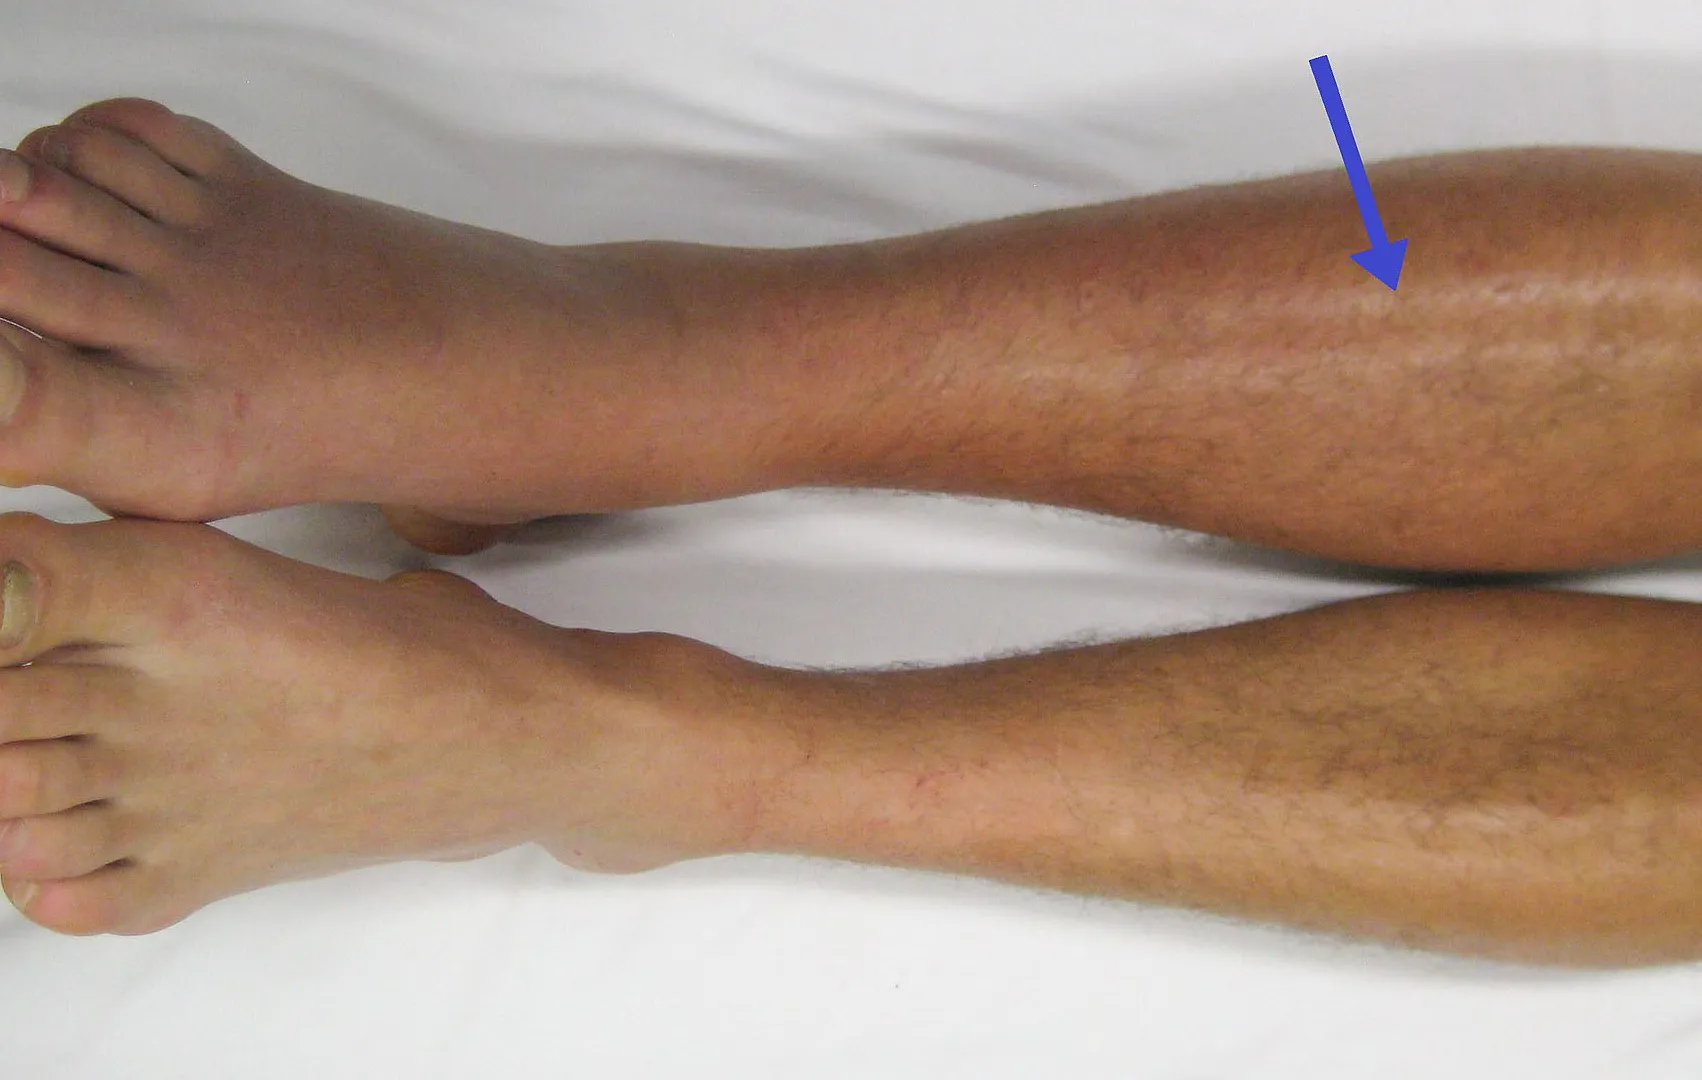

Trombosis venosa profunda (TVP)

Ocurre cuando el coágulo se forma en las venas profundas, generalmente de las piernas. Es una de las formas más comunes y peligrosas.

Síntomas más frecuentes:

-

Dolor en la pierna

Hinchazón

Enrojecimiento

Sensación de calor

Endurecimiento de la zona